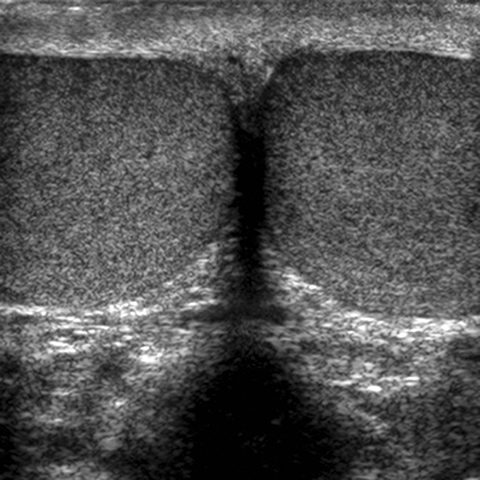

Testis, ultrasound [3 of 4]